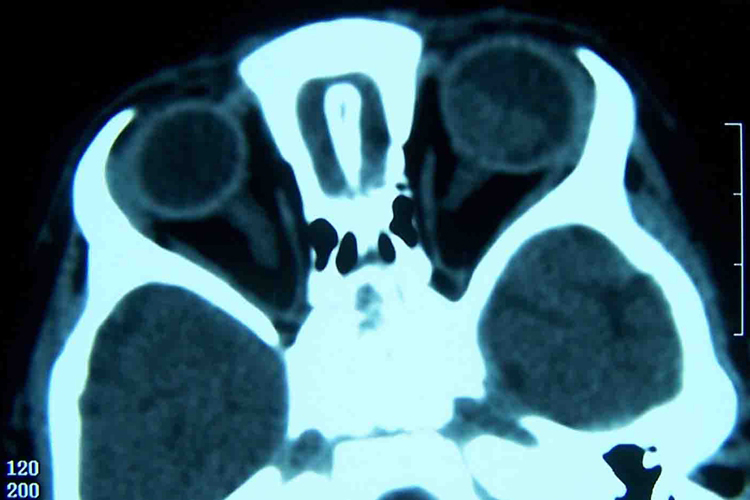

神经母细胞瘤的病因尚不清楚,患者可能会出现发热、贫血等全身症状,但肿瘤通常在体表很难发现,一般通过影像学检查发现肿瘤。

发热常为神经母细胞瘤患者的首发症状,还可有血压升高、多汗、心率增快等儿茶酚胺增高的表现。同时肿瘤早期多呈现质地较硬的结节,晚期可浸润周围组织形成巨大肿块。